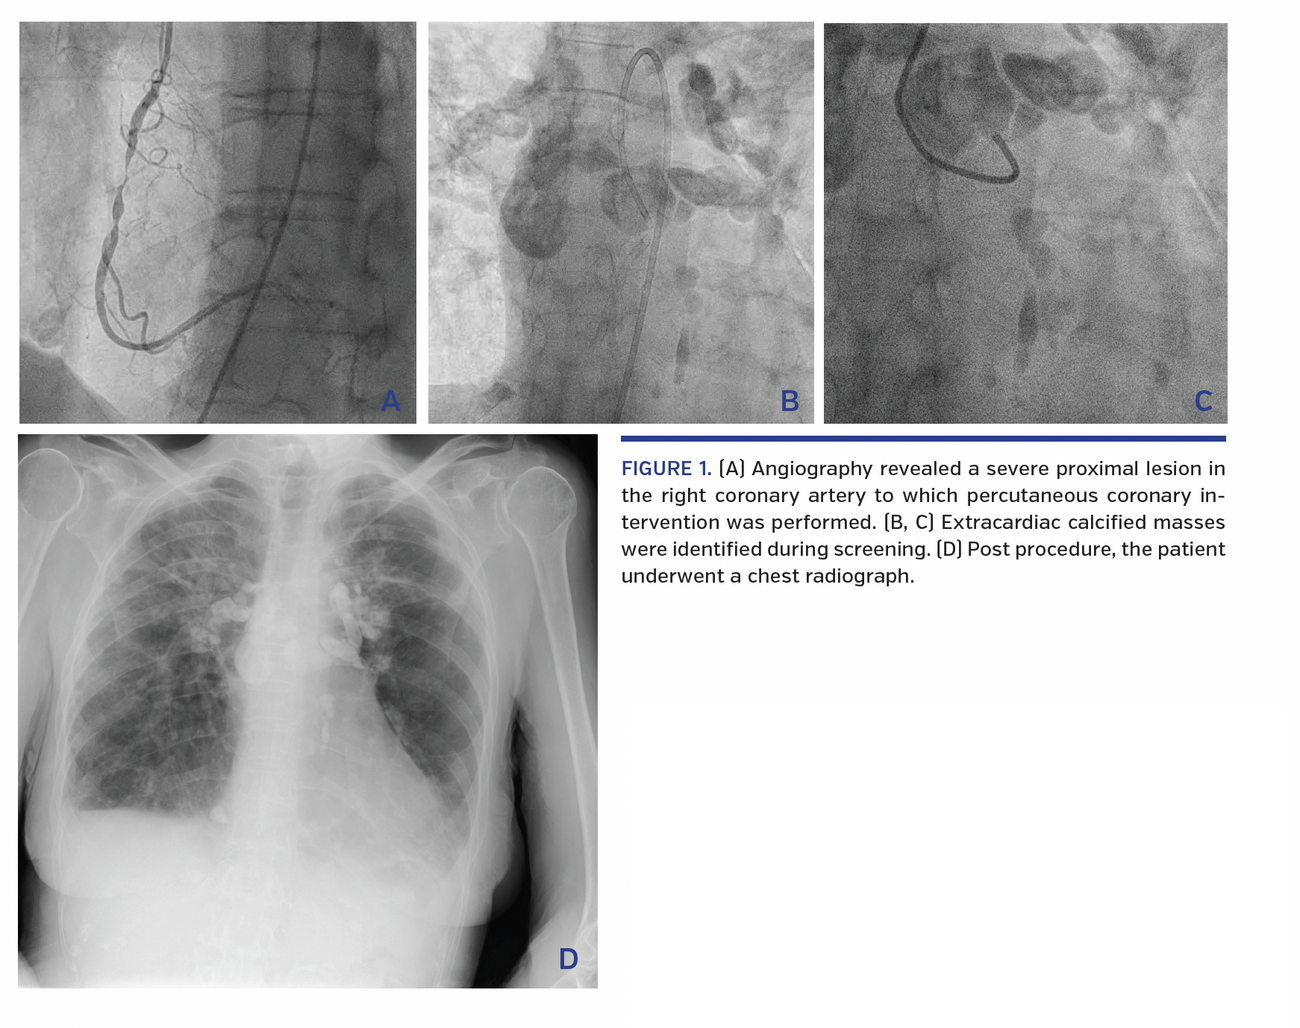

Angiography revealed a severe proximal lesion in the right coronary artery to which percutaneous coronary intervention was performed (Figure 1A). The patient experienced intermittent complete heart block during the procedure; she remained hemodynamically stable and pacing was not required. Extracardiac calcified masses were identified during screening (Figures 1B and 1C; Video 1).

Post procedure, the patient underwent a chest radiograph (Figure 1D). She was referred to the respiratory physicians and a diagnosis of sarcoidosis was confirmed on lymph node biopsy. Echocardiography showed normal left ventricular size and function, septal flattening suggestive of right ventricular pressure and volume overload, no significant valvular disease, and a small anterior pericardial effusion.